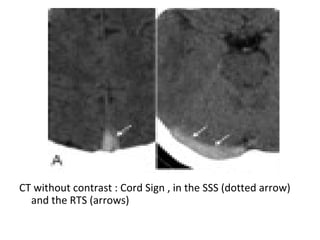

- Cord sign : is defined as a homogeneous ,

hyperattenuated appearance of thrombosed

venous sinuses , the hyperattenuated

appearance of the affected veins often being

named (the attenuated vein sign)

CT without contrast : Cord Sign , in the SSS (dotted arrow)

and the RTS (arrows)